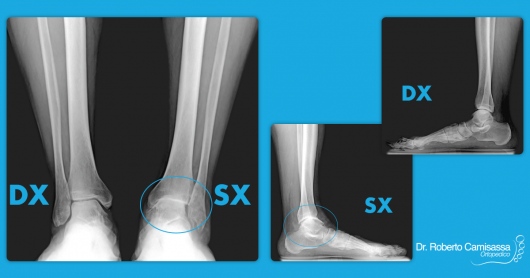

Mi dedico principalmente alle patologie a carico del Piede e della Caviglia.